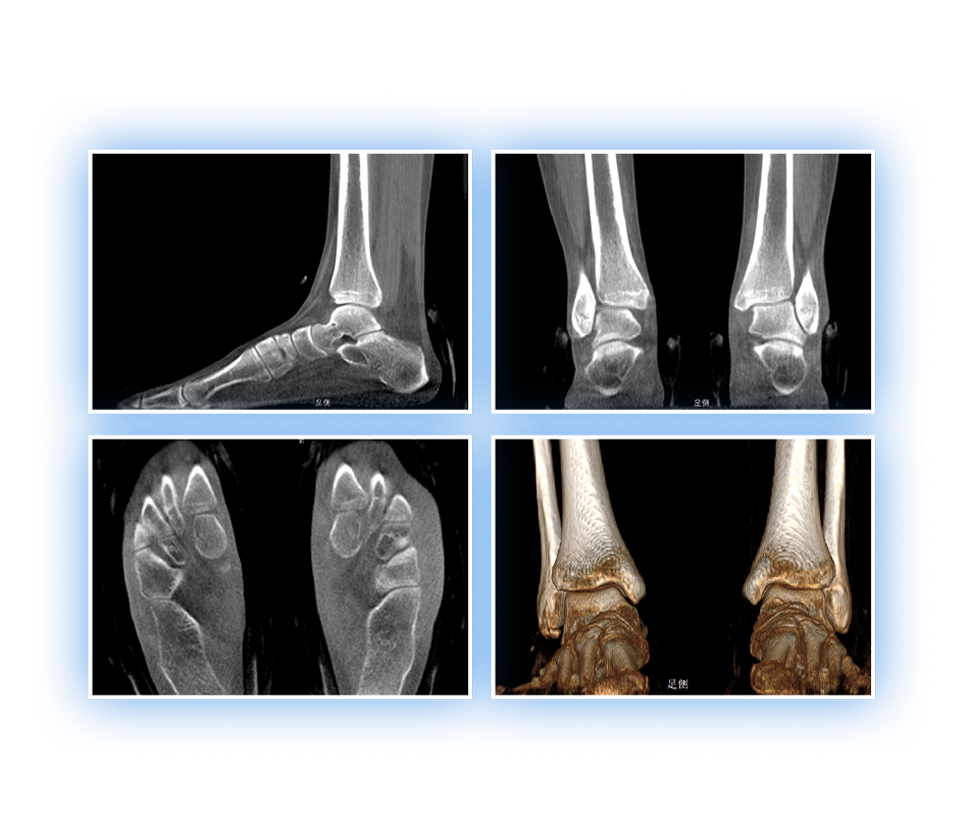

独特的负重位三维影像

填补常规CT/MR空白

助力术前规划和术后评估

• 足踝